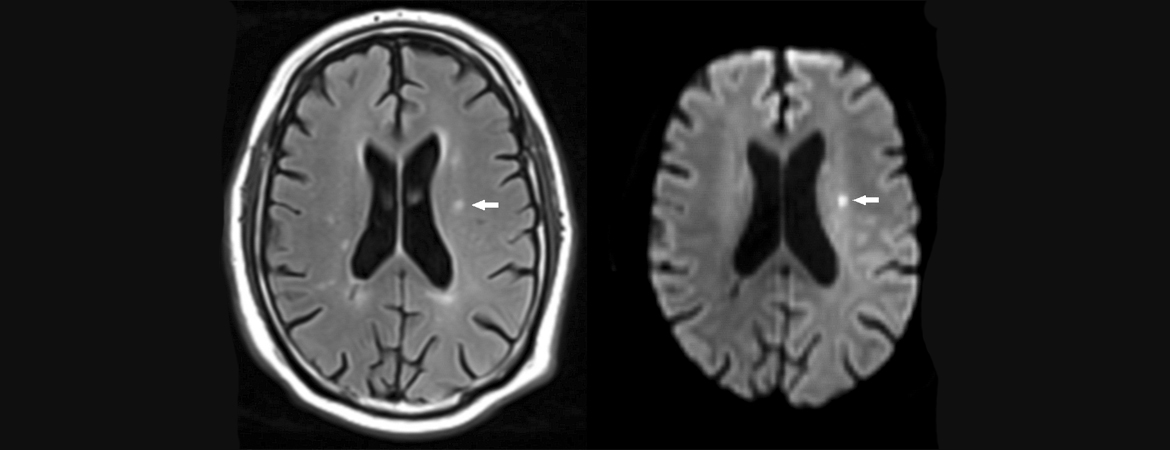

1. Design of the Swiss Atrial Fibrillation Cohort Study (Swiss-AF): structural brain damage and cognitive decline among patients with atrial fibrillation